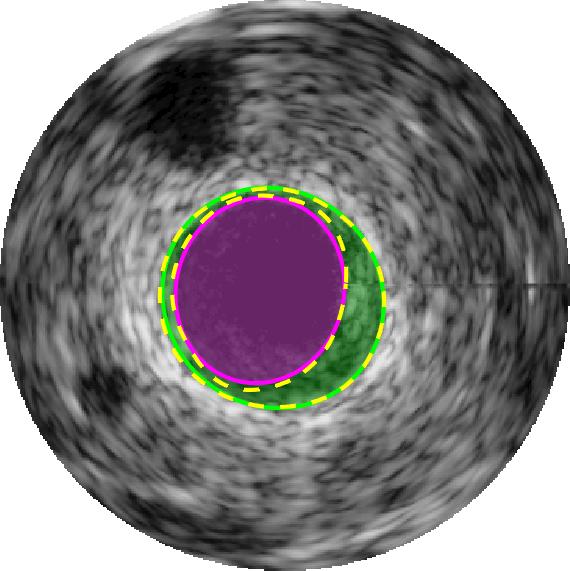

Qualitative evaluations are illustrated in Figure 4 and show the successful segmentation results of the proposed EREL selection strategy for 20 IVUS frames. The lumen areas are highlighted by the magenta colour while the media regions are green. Also, the manually annotated contours for both lumen and media are drawn as yellow dashed lines. As we can see, the chosen frames contain a variety of lumen and media morphologies.